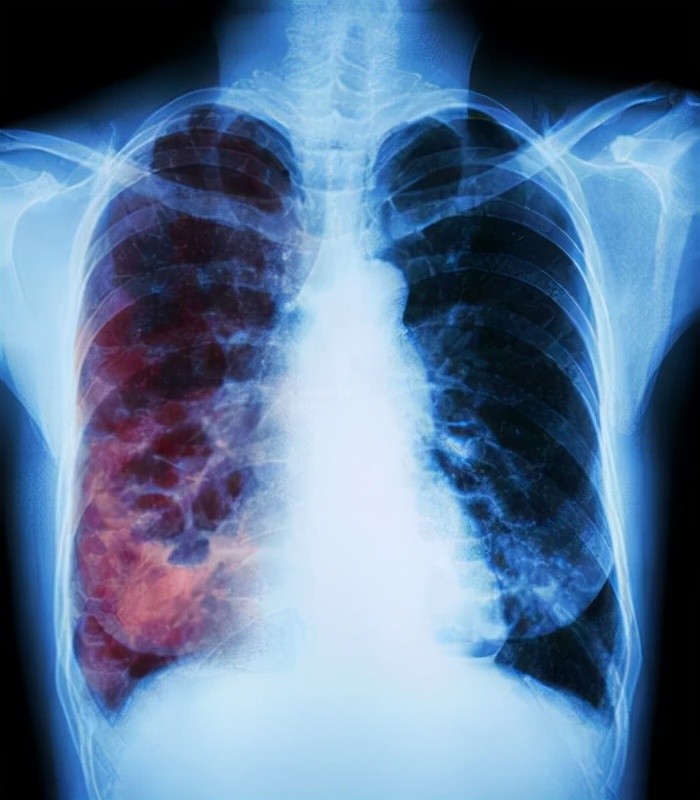

废话就不多说了,结论就是:低剂量CT,其实是目前最有应用前景的肺癌筛查手段。

肺部的CT可以想象成扫描多个胸片,而且在完全去除周围组织结构的干扰后,分辨率非常高,所以能够检查出很多不容易发现的小病灶,也能很有效地显示出低密度小病灶。

曾有学者表明,CT可以发现所有直径在8毫米以上的肺癌结节,而且对早期肺癌的检出率比胸片检查至少要提高6倍。